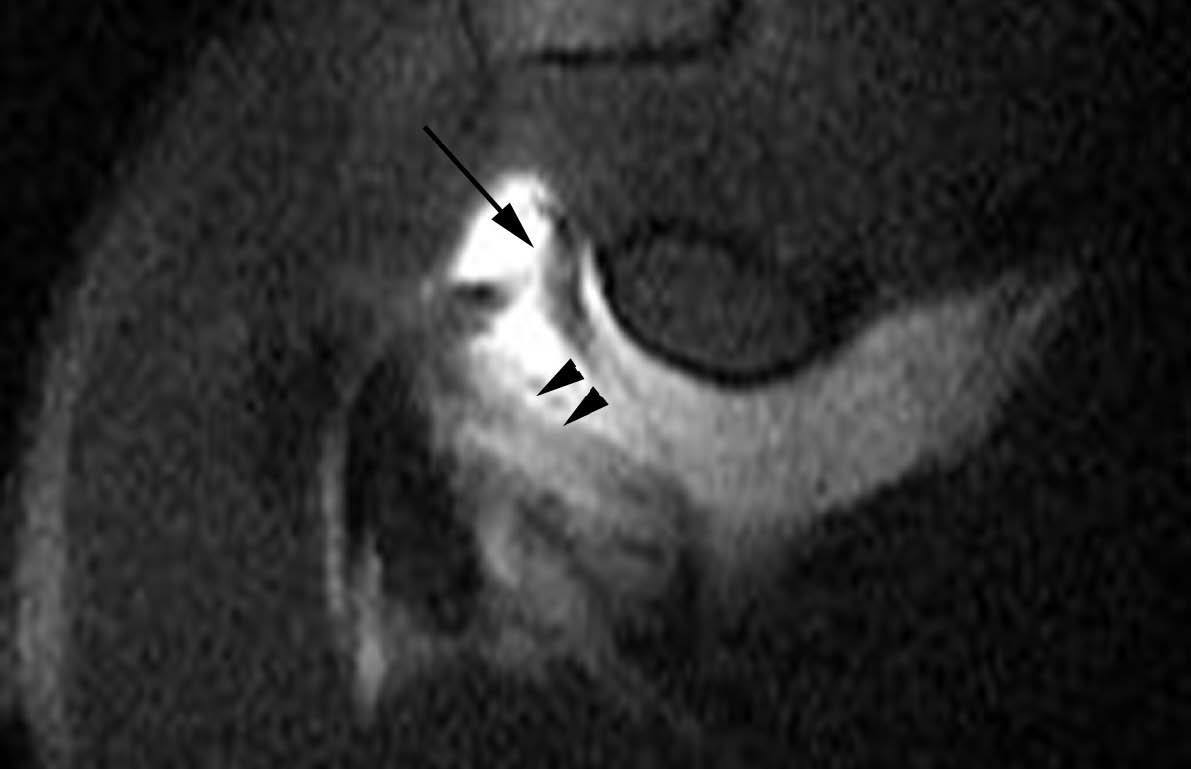

ALPSA (anterior labroliamentous periosteal avulsion)

Al igual que en el apartado anterior, existe también una separación de LG junto con la cápsula y el periostio, pero a diferencia de las lesiones de Bankart o Perthes, el LG se desplaza hacia dentro, por detrás del borde de la glenoides18 (fig. 12). La lesión de ALPSA puede cicatrizar por sinovialización (fig. 12), pero continúa siendo de carácter inestable.

Fig. 12.--ALPSA (anterior labroliamentous periosteal avulsion) agudo (A) y crónico (B). Nótese la separación del labio glenoideo y su desplazamiento posterior y medial por detrás del reborde glenoideo (flecha en A). En una fase crónica el labio glenoideo no se distingue como una estructura separada, sino como un engrosamiento de la unión entre el labio, la cápsula y el periostio (flecha en B).